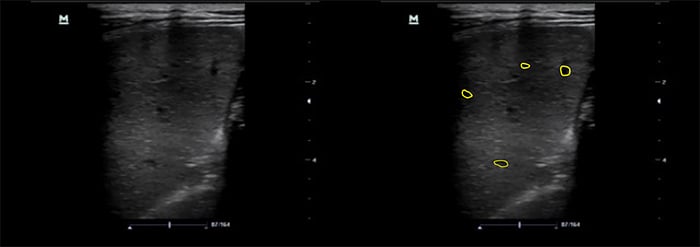

- Splenic micro abscesses: OR 1.921 (Figures 7 and 8, Videos 9 and 10)

- Micro abscesses will appear as small hypoechoic lesions. As they become numerous, they can coalesce and enlarge.

Figure 9. Spleen with microabscesses using linear transducer

Figure 10. Spleen with high frequency linear transducer, A- microabscesses and granulomatous infiltration, B- normal spleen echotexture

- The use of a high frequency linear transducer can improve your ability to identify splenic micro abscesses. 21,26-8 Freezing the image and scrolling manually can slow the image down enough to identify small micro abscesses (Figure 8).